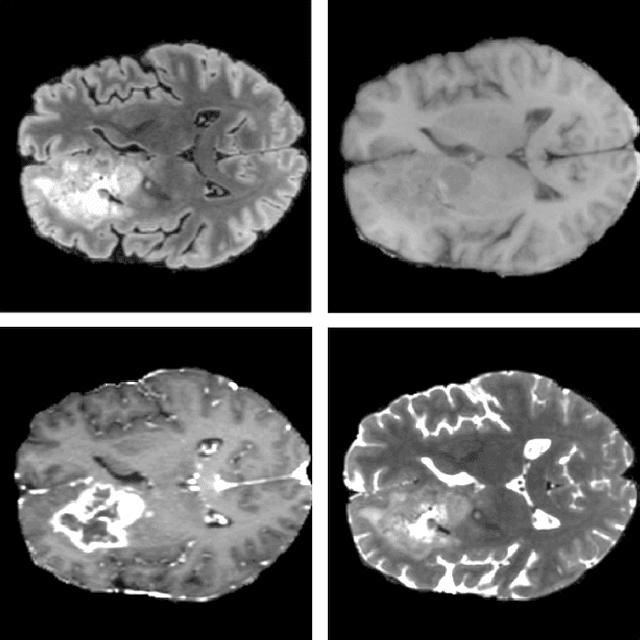

Abstract:Dynamic contrast-enhanced magnetic resonance imaging (DCE-MRI) plays an important role in diagnosis and grading of brain tumor. Although manual DCE biomarker extraction algorithms boost the diagnostic yield of DCE-MRI by providing quantitative information on tumor prognosis and prediction, they are time-consuming and prone to human error. In this paper, we propose a fully-automated, end-to-end system for DCE-MRI analysis of brain tumors. Our deep learning-powered technique does not require any user interaction, it yields reproducible results, and it is rigorously validated against benchmark (BraTS'17 for tumor segmentation, and a test dataset released by the Quantitative Imaging Biomarkers Alliance for the contrast-concentration fitting) and clinical (44 low-grade glioma patients) data. Also, we introduce a cubic model of the vascular input function used for pharmacokinetic modeling which significantly decreases the fitting error when compared with the state of the art, alongside a real-time algorithm for determination of the vascular input region. An extensive experimental study, backed up with statistical tests, showed that our system delivers state-of-the-art results (in terms of segmentation accuracy and contrast-concentration fitting) while requiring less than 3 minutes to process an entire input DCE-MRI study using a single GPU.